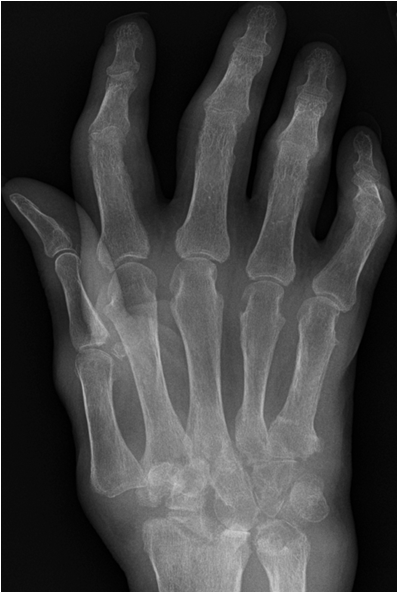

Rheumatoid arthritis may involve any synovial joint. The sacroiliac joints are involved only infrequently. The greatest involvement is in the small joints of the hands, wrists and feet with sparing of the distal interphalangeal joints. In early stages there may be only soft tissue swelling and juxta-articular osteoporosis. Next joint space narrowing and early erosive changes are seen.

In general, the presence of erosions bespeaks some type of inflammatory disease, whether the erosions are due to synovial hypertrophy, crystalline deposits, or infection. In rheumatoid arthritis, the erosions follow the development of an inflammatory proliferation of the synovium, called pannus. As this pannus increases in amount, it begins to cause erosions of the chondral surface. As the pannus increases further in amount, one begins to see erosions at the periarticular "bare" areas. These "bare" areas refer to bone within the synovial space which is not covered by articular cartilage. The articular cartilage tends to protect the bone that it covers. The marginal "bare" areas are not covered by cartilage, and the earliest erosions of rheumatoid arthritis are seen here.

Fig. 15. Rheumatoid arthritis. A) Early erosive changes are seen at the bare areas of the second and thirs metacarpal-pahalangeal joint. B.) In a patient with long standing rheumatoid arthritis marked destruction of carpal bones and styloid process has occurred. Note luxation of the first MCP joint, erosions at the other MCP joints and generalized osteoporosis.